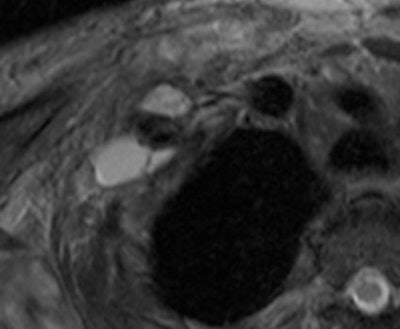

Patients ranged in age from 18 to 84 years. Their lesions detected by MRI represented a mix, including 35 root avulsions and brachial plexus cord injuries, 22 primary or secondary tumors, and four each entrapment syndromes, fibrous scars, and Parsonage-Turner syndrome.

Overall, the sensitivity for the total number of examinations analyzed on a per-patient basis was 81% and specificity was 91%. Analyzed by findings, mass lesions had the highest positive predictive value at 95%, followed by traumatic injury at 91%. The lowest was for entrapment syndromes, at 80% and 66% for post-treatment evaluation. Negative predictive values ranged from a low of 83% for traumatic injury to a high of 2% for mass lesions and post-treatment evaluations.